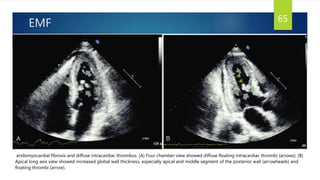

EMF 65

endomyocardial fibrosis and diffuse intracardiac thrombus. (A) Four chamber view showed diffuse floating intracardiac thrombi (arrows). (B)

Apical long axis view showed increased global wall thickness, especially apical and middle segment of the posterior wall (arrowheads) and

floating thrombi (arrow).

EMF 65 endomyocardial fibrosisand diffuse intracardiac thrombus. (A) Four chamber view showed diffuse floating intracardiac thrombi (arrows). (B) Apical long axis view showed increased global wall thickness, especially apical and middle segment of the posterior wall (arrowheads) and floating thrombi (arrow).